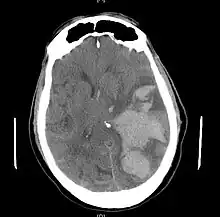

Brain herniation is a potentially deadly side effect of very high pressure within the skull that occurs when a part of the brain is squeezed across structures within the skull. The brain can shift across such structures as the falx cerebri, the tentorium cerebelli, and even through the foramen magnum (the hole in the base of the skull through which the spinal cord connects with the brain). Herniation can be caused by a number of factors that cause a mass effect and increase intracranial pressure (ICP): these include traumatic brain injury, intracranial hemorrhage, or brain tumor.[1]

Herniation can also occur in the absence of high ICP when mass lesions such as hematomas occur at the borders of brain compartments. In such cases local pressure is increased at the place where the herniation occurs, but this pressure is not transmitted to the rest of the brain, and therefore does not register as an increase in ICP.[2]

Because herniation puts extreme pressure on parts of the brain and thereby cuts off the blood supply to various parts of the brain, it is often fatal. Therefore, extreme measures are taken in hospital settings to prevent the condition by reducing intracranial pressure, or decompressing (draining) a hematoma which is putting local pressure on a part of the brain.

Treatment involves removal of the etiologic mass and decompressive craniectomy. Brain herniation can cause severe disability or death. In fact, when herniation is visible on a CT scan, the prognosis for a meaningful recovery of neurological function is poor.[2] The patient may become paralyzed on the same side as the lesion causing the pressure, or damage to parts of the brain caused by herniation may cause paralysis on the side opposite the lesion.[11] Damage to the midbrain, which contains the reticular activating network which regulates consciousness, will result in coma.[11] Damage to the cardio-respiratory centers in the medulla oblongata will cause respiratory arrest and (secondarily) cardiac arrest.[11] Investigation is underway regarding the use of neuroprotective agents during the prolonged post-traumatic period of brain hypersensitivity associated with the syndrome.[17]